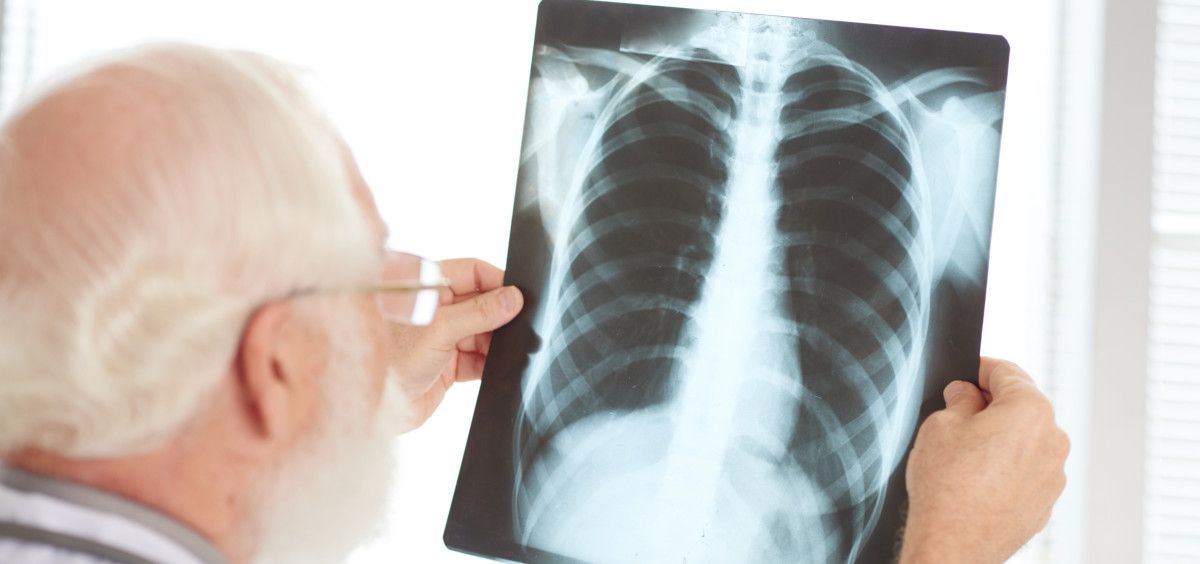

El cáncer de pulmón, por lo general, no suele presentar sintomatología en sus primeros estadios, sin embargo, cuando aparecen suelen presentar tos, adelgazamiento, fatiga crónica o infecciones pulmonares persistentes. Para detectar esta tipología de cáncer se pueden realizar pruebas de diagnóstico por imagen (con rayos x o TC scan), siendo imprescindible la realización de una biopsia para conocer el tipo de cáncer de pulmón, así como sus características genéticas.